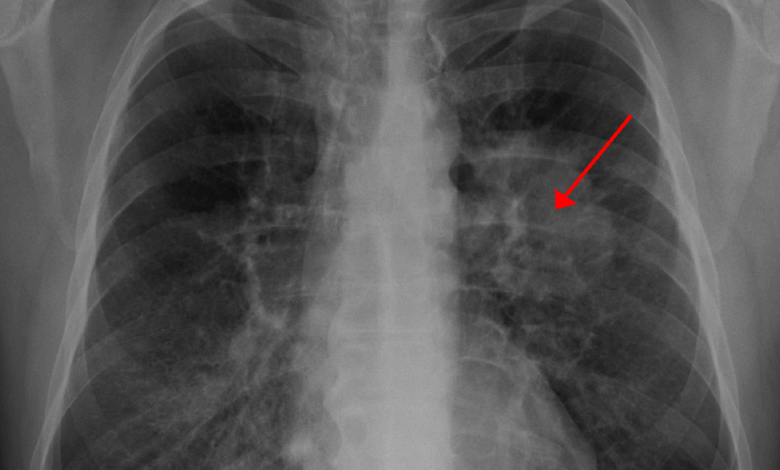

Clinical Oncologist at the Korle Bu Teaching Hospital, Dr Nana Ama Wadee, has raised concern over Ghana’s rising lung cancer deaths, warning that many patients are dying because the disease is often detected too late.

Speaking on Joy FM’s Super Morning Show on Thursday, October 16, as part of Joy Cancer Awareness Month, Dr Wadee explained that while lung cancer is the leading cause of cancer deaths worldwide, Ghana’s situation is particularly troubling because most patients report to the hospital when the disease is already advanced.

“We believe there are a lot of underdiagnosed cases,” she said. “Many patients are treated over and over again for other respiratory conditions such as tuberculosis or pneumonia before it is eventually found to be lung cancer.”

“Early lung cancer can be completely asymptomatic. When symptoms appear, patients may have a cough, breathlessness, chest pain, or cough up blood.”